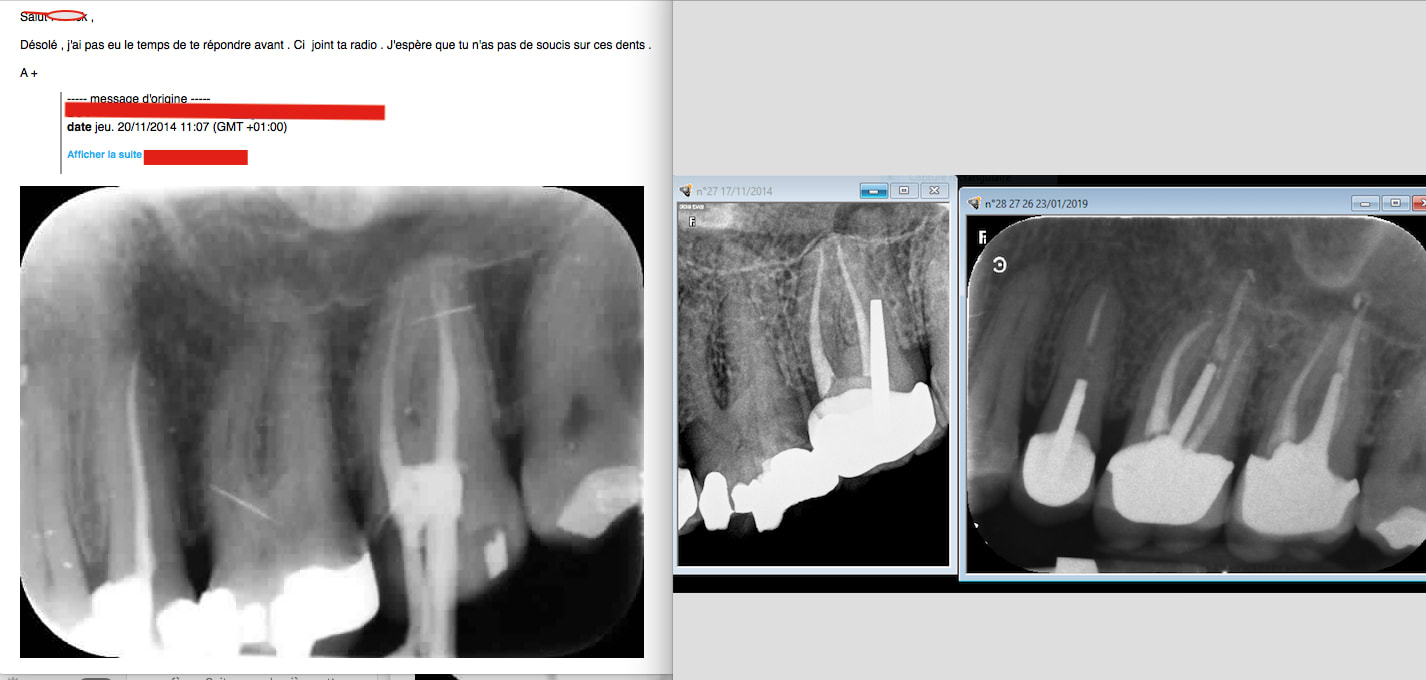

J'aimais bien quand Chicot postait ses endos.

Ah c'est toi qui l'a récupéré!-)

Pour personnellement en avoir fait les frais je peux te dire que les radios cones coupés ont un intérêt. Tu peux m'expliquer comment le cone de gutta en palatin a disparu ? Je coupe les 3 cones en meme temps et je ne m'aperçois pas qu'il y en a un qui s'est barré. Je ne pense pas que ça soit volontaire entre confrères ça ne se fait pas. Non ? -)))